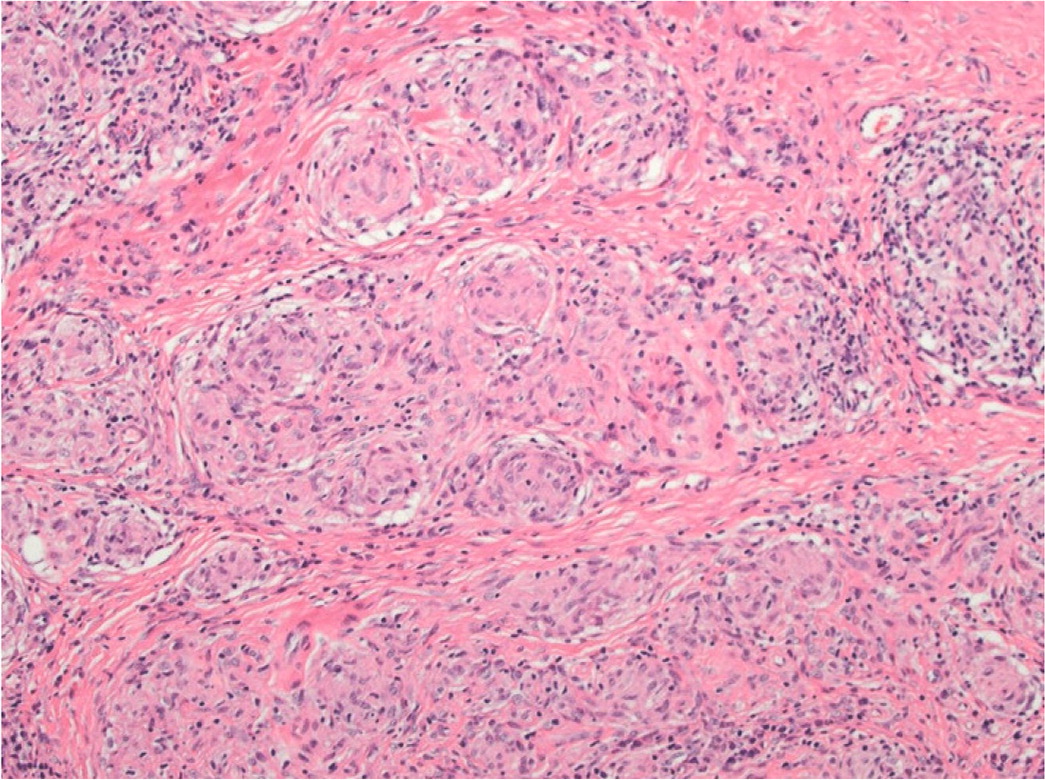

A tissue biopsy of cutaneous lesions or peripheral lymph nodes is the least invasive and safest option for diagnosis. Histopathologic findings of sarcoidosis are characterized by noncaseating granulomas consisting of aggregates of epithelioid histiocytes, giant cells, and mature macrophages35 (Figure 4). Lymphocyte composition is primarily CD4 T cells and a few CD8 lymphocytes. Patients without peripheral lesions may require bronchoscopy procedures such as transbronchial biopsy and endobronchial ultrasound-guided transbronchial needle aspiration, which is 80% to 90% sensitive, with complication rates of less than 1%.23,27,36 Bronchoalveolar lavage shows lymphocytosis and a CD4: CD8 T-cell ratio greater than 3.5 but low sensitivity (53% to 59%).24

FIGURE 4.

Histopathology of sarcoidosis. Hematoxylin and eosin-stained x400 magnification. Noncaseating granulomas in the dermis with multinucleated histiocytes and lymphocytic inflammation.